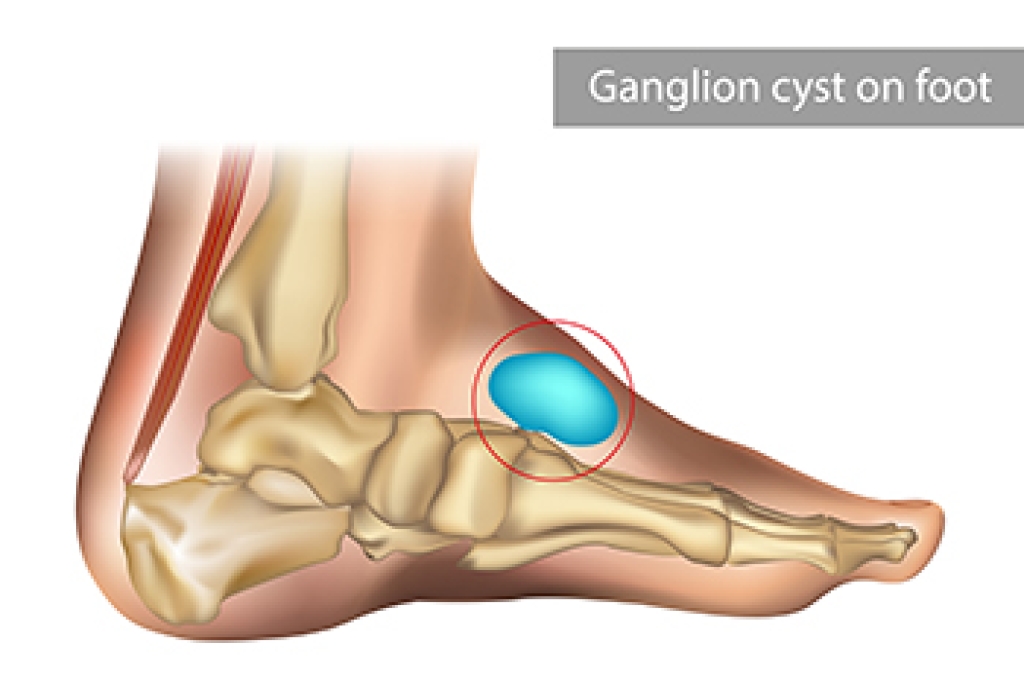

A ganglion cyst is a non-cancerous lump filled with a gel-like fluid. Ganglion cysts typically develop along a tendon or joint, such as the ankle or on the top of the foot. It is generally not painful, unless it presses on a nearby nerve. This non-cancerous growth may appear round or oval, and its location may inhibit foot or ankle movement. A ganglion cyst usually develops over time, often as the result of repeated irritation. This causes fluid to leak out from a tendon tunnel and begin to swell under the skin. Formation of a ganglion cyst also may be the result of trauma or an underlying medical condition, such as arthritis. A podiatrist can draw fluid from a cyst as well as do imaging tests to determine what it is and what may be causing it. Often a ganglion cyst will simply go away on its own, but it can be treated if it is causing pain or irritation. Treatment options include drawing out the fluid and injecting anti-inflammatory medication, and removing the cyst entirely. If you think you may have developed a ganglion cyst, please consult a podiatrist for a diagnostic test and treatment plan.